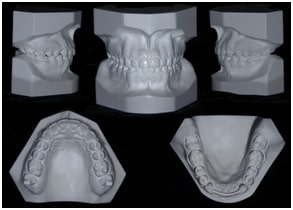

DOCUMENTAÇÕES ORTODÔNTICAS

Modelos em Gesso

Fotografias Intra-Orais e Extra-Orais